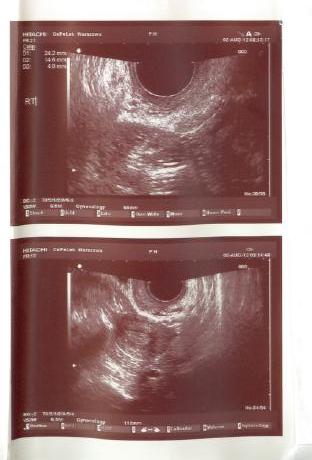

Nie mierzyłam tempki bo pewnie i tak by była zaburzona bo alkohol itd... @ dalej nie ma... znowu ten cykl się wydłuża... Wrr